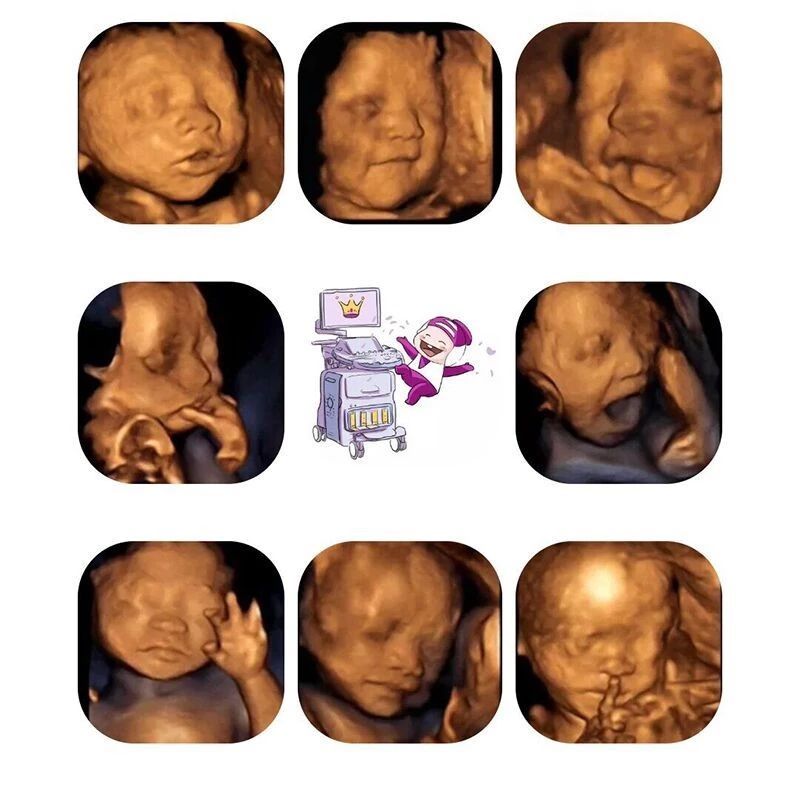

超声影像(四维彩超)不再是仅仅感觉宝宝的呼吸和运动,而是可以亲眼目睹他们的一举一动和乖巧的秀容。让宝爸宝妈提前跟胎宝宝”见面“,看到胎儿在母体内的实时动态,如微笑、打呵欠、皱眉头、做鬼脸、吸手指、伸懒腰、吐舌头等。

新百佳妇儿超声影像(四维彩超)可直观、立体、多方位观察胎宝宝生长发育情况,显示胎宝宝的实时动态”动画“,直观了解宝宝的一举一动,为胎儿健康保驾护航。